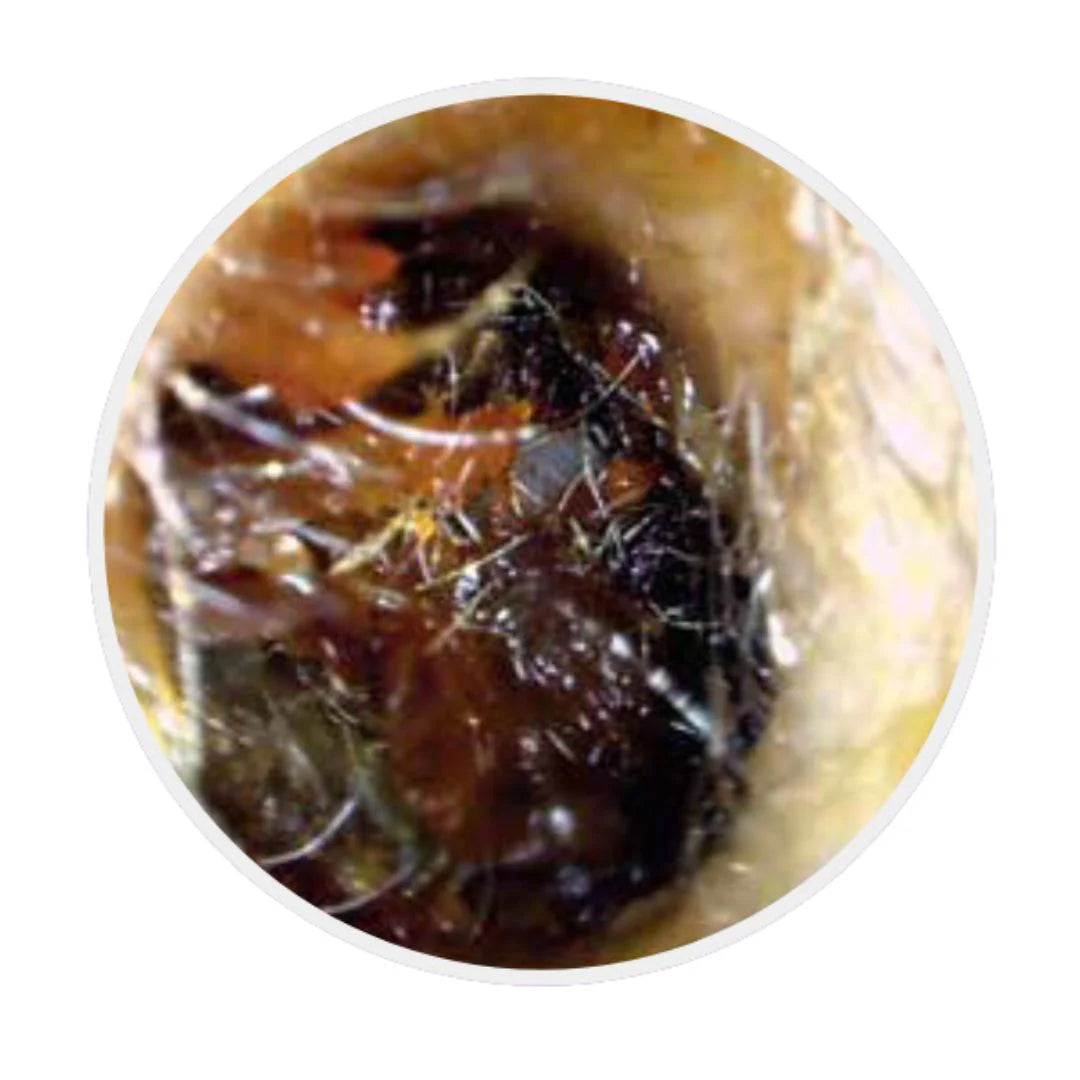

Avant